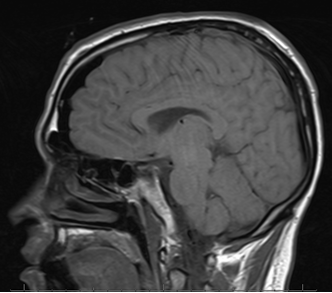

I finally requested my MRI scans from UT Southwestern. At first they said no, then I said please and NO ONE, not even fancy hospitals can deny a request when you utter the magic word.

Moving on, I received said scans in the mail a few days ago and have selected a few to show you.

The next scan was taken on the 4th of September, in that foul year of our Lord, 2009. This was the day after the cavernoma was removed. Squeaky clean, no?